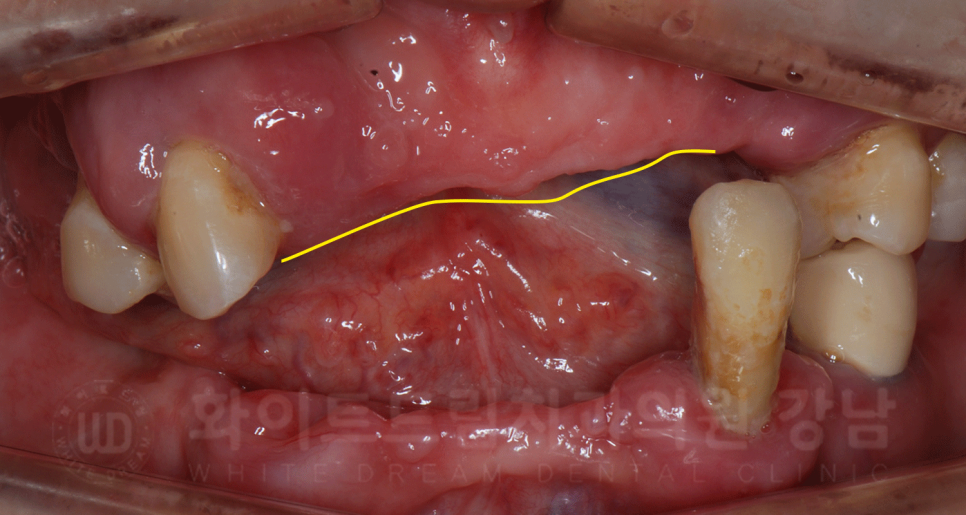

틀니를 뺀 후 구내 상태입니다.

근육이 운동을 하지 않으면 점점 약해지는 것처럼,

우리 잇몸도 치아가 전달해 주던 힘을 못 받게 되면

점점 위축되면서 모양이 변하게 됩니다.

▲ 치아가 있는 곳과 없는 곳의 잇몸뼈 차이가 명확하게 보이시나요?

치주염으로 잇몸이 발적되어 있는 상태를 고려해도 잇몸뼈 두께의 차이가 눈에 보실 겁니다.

이러한 이유로 시간이 지나면 점점 기존의 틀니가 맞지 않고 불편해지는 것인데요.

환자분도 틀니를 몇 번 수정하고 써봤지만 통증이 점점 심해졌다고 하셨습니다.